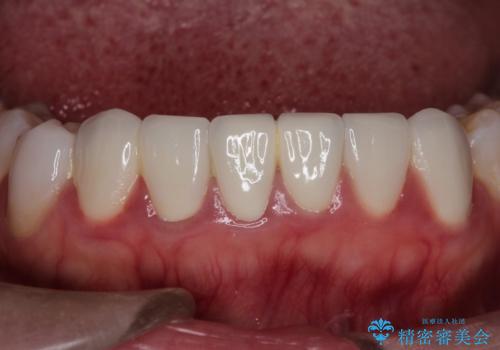

【オールセラミック】下の前歯が痛い。

- 以前に治療した前歯が痛むことを主訴に来院されました。

根っこに病気があり、根管治療から被せ物まで治療を行いました。

根管治療を行った後、3ヶ月間治癒の確認をしてからオールセラミックスペシャルで治療を行いました。